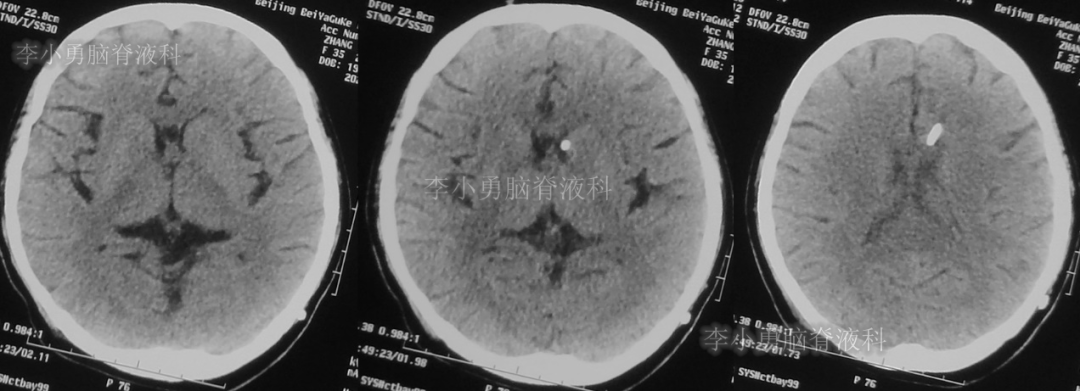

次日,即2018年11月11日,患者第2次到给予脑室腹腔分流术的医院,复查头颅CT(图-5)见脑积水仍严重。

图-5:2018年11月11日头颅CT

但第2次调压后2周,即2018年11月28日,再次到当地的第1家医院复查头颅CT(图-6)见脑积水缓解。

图-6:2018年11月28日头颅CT